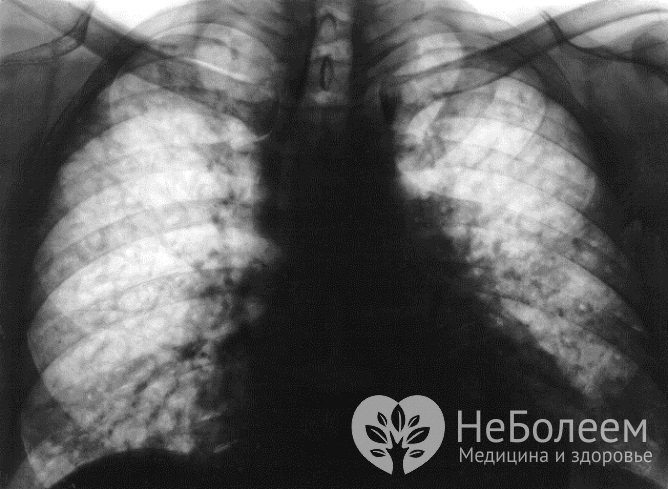

В ходе рентгенологического исследования при экзогенном аллергическом альвеолите выявляется снижение прозрачности легочной ткани с образованием большого количества мелкоочаговых теней. С целью подтверждения диагноза проводится лабораторная иммунологическая диагностика, провокационные ингаляционные тесты, компьютерная томография легких. В диагностически сложных случаях прибегают к биопсии легочной ткани с последующим гистологическим исследованием полученного материала.

Экзогенный альвеолит легких на рентгеновском снимкеВ случае идиопатического фиброзирующего альвеолита на рентгенограмме легких с двух сторон определяются мелкоочаговые диффузные изменения, более выраженные в нижних отделах. На поздних стадиях заболевания в легочной ткани выявляются вторичные кистозные изменения. Данные компьютерной томографии легких позволяют определить участок измененной легочной ткани для последующего проведения биопсии. Результаты электрокардиограммы указывают на наличие гипертрофии и перегрузки правых отделов сердца.

Рентгенологические изменения при остром токсическом фиброзирующем альвеолите могут отсутствовать. В дальнейшем определяются деформация и диффузное усиление легочного рисунка, а также диффузный фиброз.